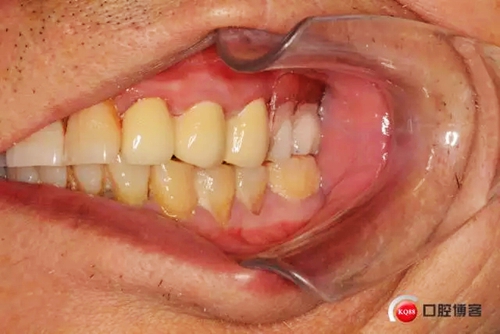

主訴:求鑲牙,解決咀嚼功能及食物嵌塞問(wèn)題

兩年前患者外院口腔鑲固定義齒修復(fù)使用不久牙冠脫落基牙折斷,又繼續(xù)修復(fù)可摘局部義齒,惡心、無(wú)法咀嚼且食物嵌塞嚴(yán)重,前來(lái)本院求重新修復(fù)。

口腔檢查:22深齲有瘺管 23 24殘根,15近遠(yuǎn)中間隙(機(jī)械性片切造成),x片22 23 24 根尖低密度陰影

患者初診口腔情況15號(hào)牙為原做可摘局部義齒做卡環(huán)預(yù)備,真“專家”的活